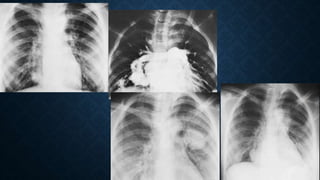

• La radiografía de tórax no detecta de

forma fiables MAVPs menores de 20mm

o que no se detecte cuando se encuentra

en surcos costofrénicos, región

retrocardiaca o el hilio proximal.